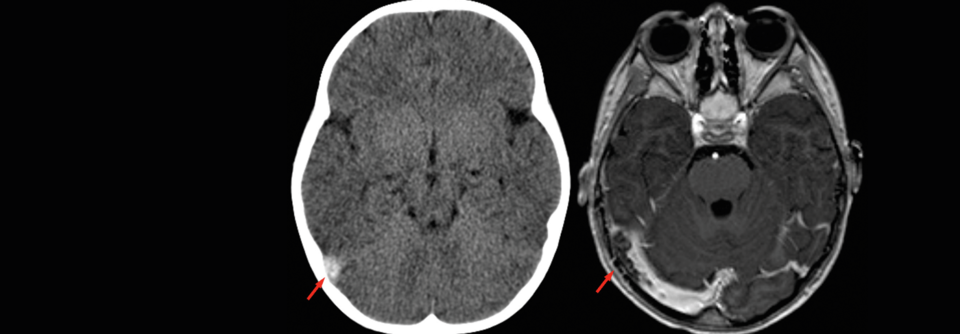

Anzeichen für eine Sinusvenenthrombose (Pfeil) sind kontinuierlich zunehmende Schmerzen und epileptische Anfälle.

Anzeichen für eine Sinusvenenthrombose (Pfeil) sind kontinuierlich zunehmende Schmerzen und epileptische Anfälle. © wikimedia/Hellerhoff